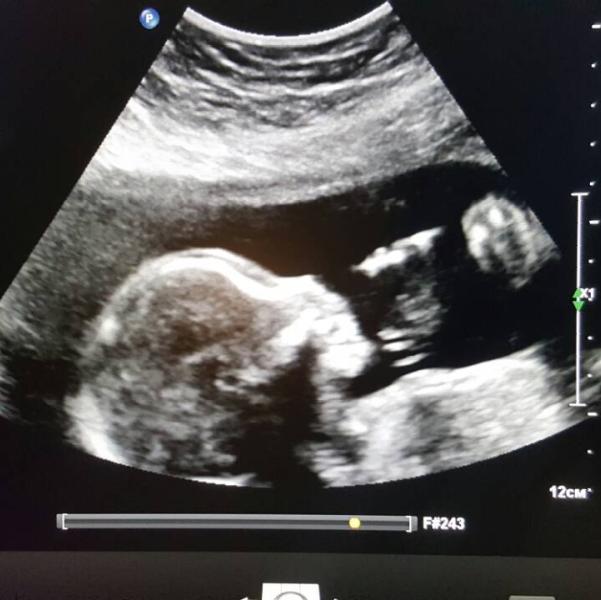

Мамочки привет. Сегодня была на УЗИ, все хорошо, мой сыночек сидит, кулачки держит 😘😘😘😘😘😘